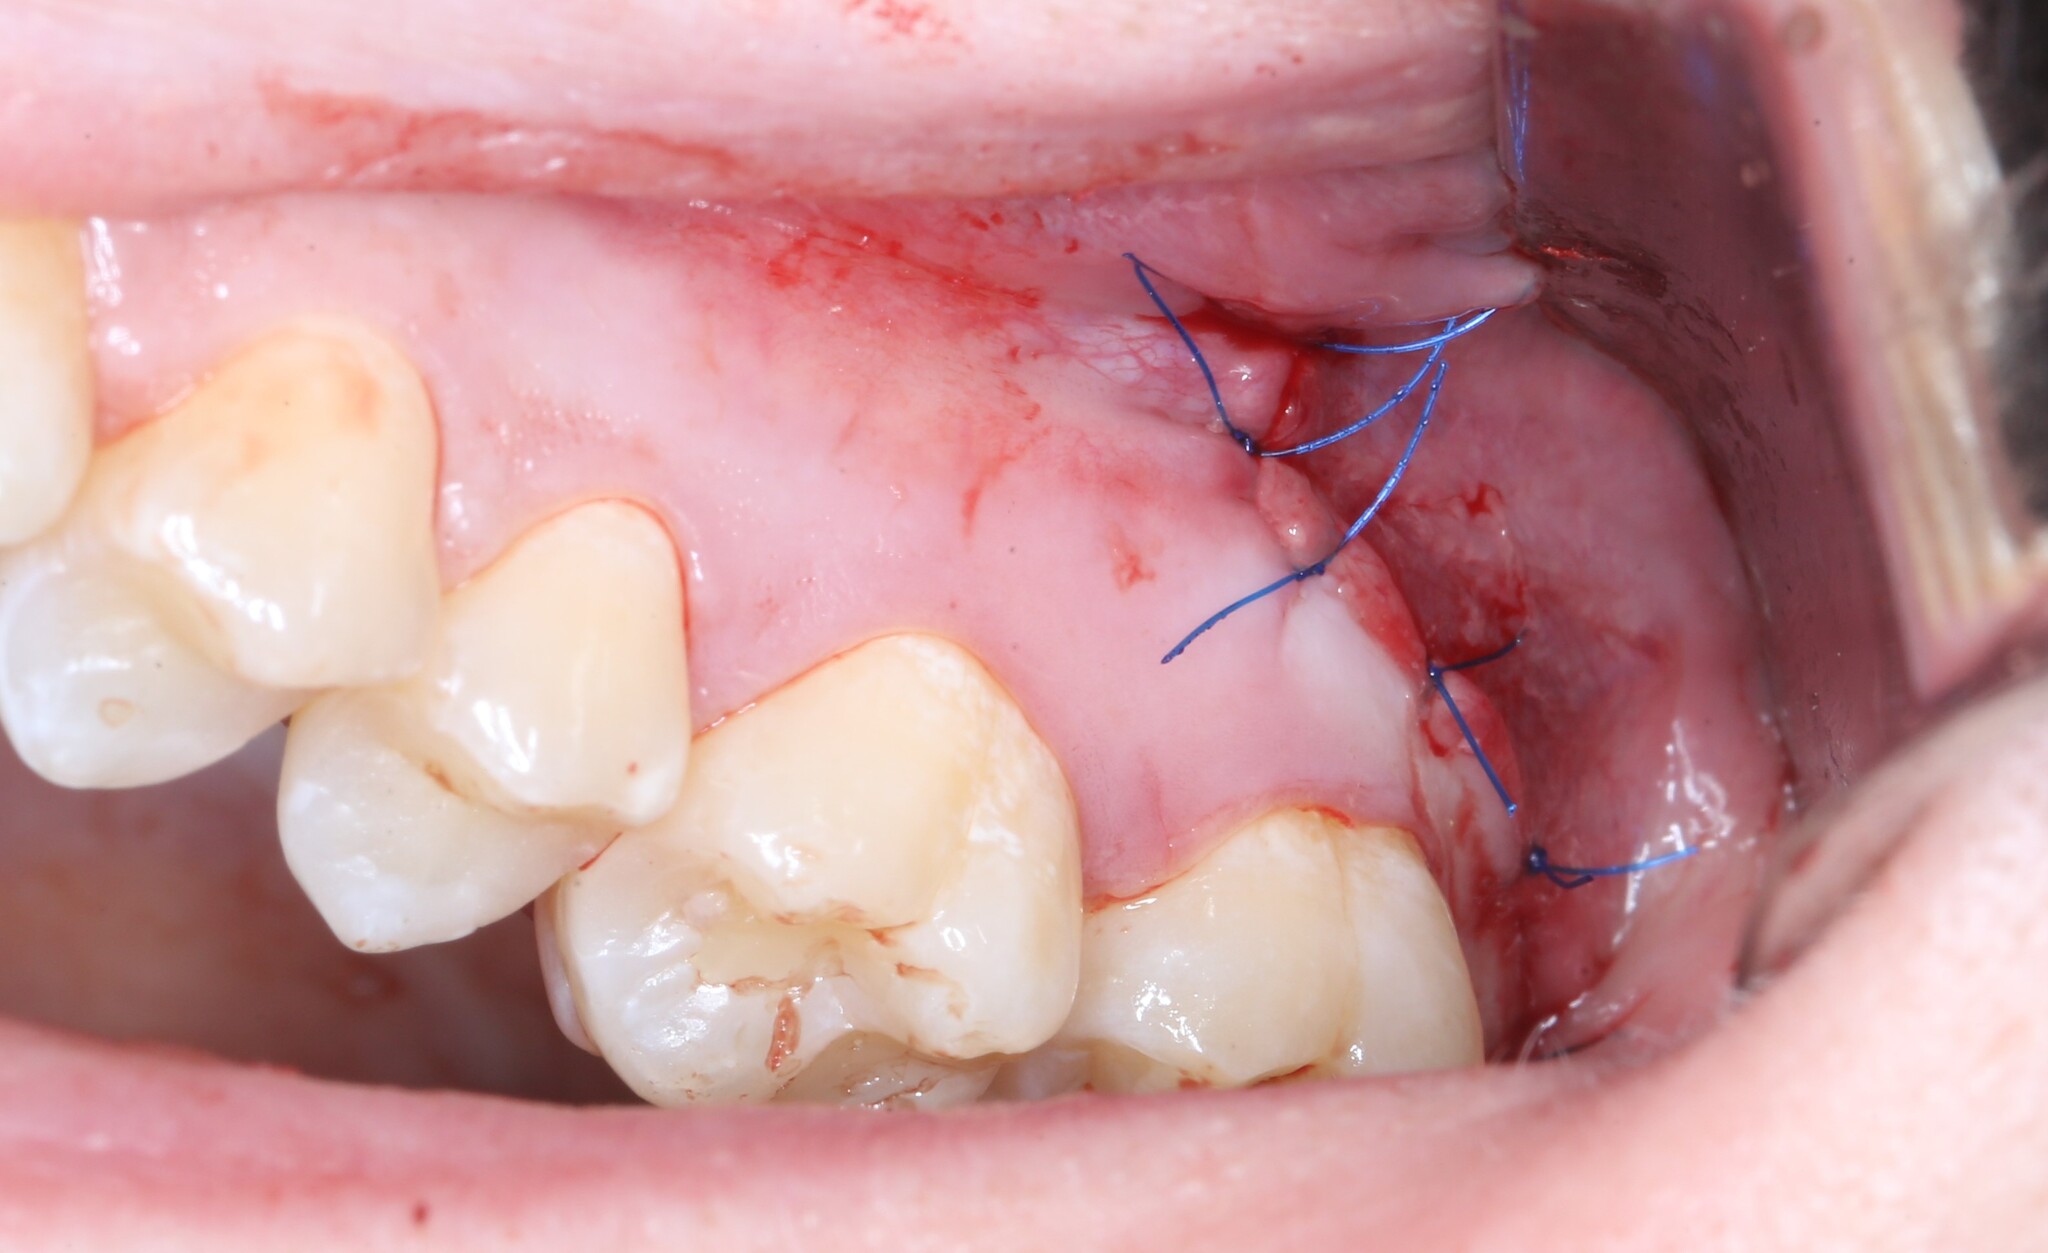

Вот так выглядит область, в которую мы планируем вмешаться:

Я сделал анестезию, разрез и отслоил слизисто-надкостнечный лоскут:

Далее швы и в общем-то и все: